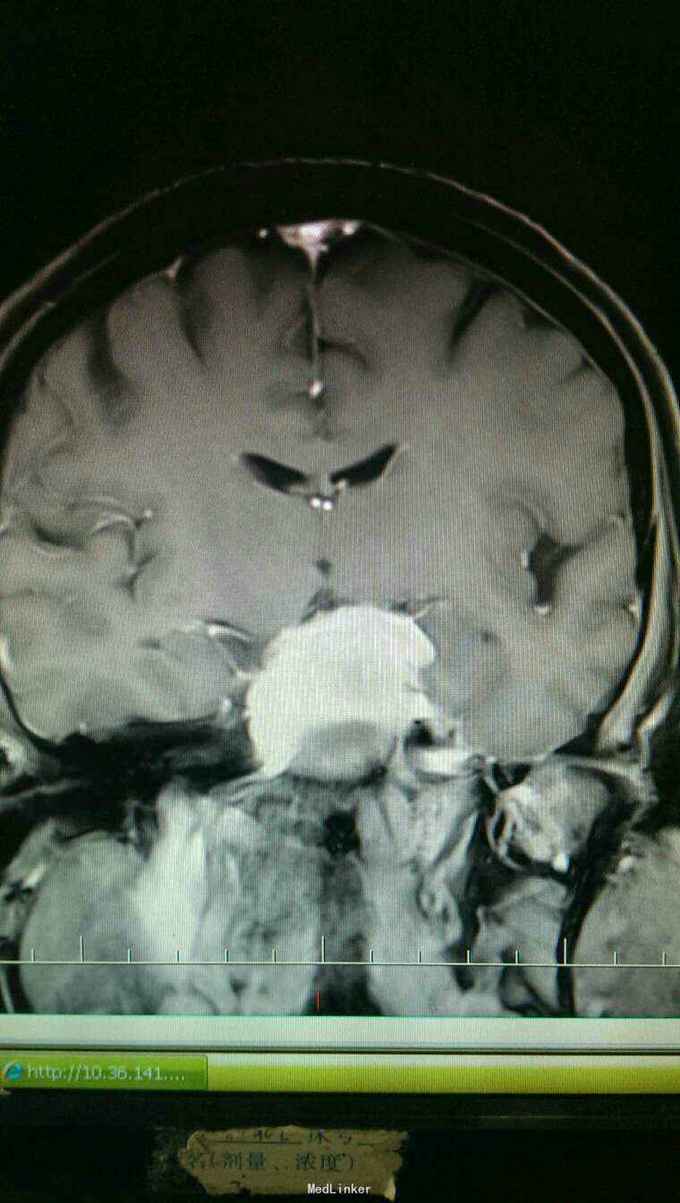

患者以头晕伴走路不稳一个月为主诉入院。患者于入院一个月前自觉头晕,无头痛,无恶心,呕吐。走路不稳,无四肢抽搐及二便失禁。

查体:神志清楚,语言流利。双侧瞳孔等大正圆,直径3.0毫米,光反射灵敏。饮水呛咳,无声音嘶哑。颈软,四肢肌力正常,生理反射存在,病理反射未引出。

入院诊断:岩斜区脑膜瘤。完善术前准备,于全麻下行右侧颞下入路,岩斜区肿瘤切除,术中保留拉贝静脉,剪开小脑幕,近全切除肿瘤。

患者术后病情稳定,岩斜区位于颞骨岩部背面与枕骨斜坡部的岩斜裂汇合处,从岩骨尖至颈静脉孔。内侧至斜坡中线,外侧至第Ⅴ、Ⅶ和Ⅷ脑神经,上缘为鞍背,下缘为颈静脉孔水平;下方为枕骨大孔区。岩斜区脑膜瘤由于位置深,毗邻重要解剖结构,很难实现肿瘤全切除,且有较高的术后致残率,一直是神经外科手术的治疗难点。颅内脑膜瘤约0.3%~1.0%起源于岩斜区,是岩斜区最常见病变。它向上可侵犯岩骨尖、小脑幕、Meckel腔、鞍旁和海绵窦;向下侵犯内听道和颈静脉孔;向内侧达脑干和椎-基底动脉。当肿瘤很大时,可包绕同侧Ⅲ~Ⅺ脑神经。患者临床可表现头痛、复杂的脑神经麻痹、共济失调等症状,严重者表现为偏瘫、认知功能障碍。岩斜区脑膜瘤多数表现良性过程,目前,仍以手术切除为首选治疗方式。 岩斜区脑膜瘤手术技术非常关键,需要熟悉岩斜区解剖关系并有丰富的显微操作经验。在术前放置腰穿引流,或术中甘露醇应用可明显降低脑组织压力,减少牵拉造成的副损伤。提前对脑膜瘤基底的处理可有效避免肿瘤持续出血造成的蛛网膜界面消失。肿瘤的生长将神经、血管拉伸或包绕,尤其是复发的肿瘤,会破坏蛛网膜界面,侵犯脑干软脑膜。手术时应仔细分辨和保护。肿瘤囊壁与神经、血管外膜和脑干粘连,不应勉强分离,以保护下方结构。 待术后平稳复查头Ct。